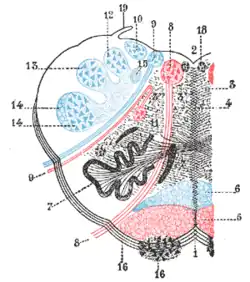

| Medulla oblongata, shown by a transverse section passing through the middle of the olive. (Lateral medullary syndrome can affect structures in upper left: #9=vagus nerve, #10=acoustic nucleus, #12=nucleus gracilis, #13=nucleus cuneatus, #14=head of posterior column and lower sensory root of trigeminal nerve and #19=Ligula.) | |